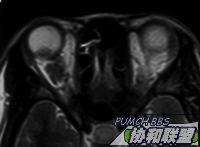

患者女性30岁。主诉右眼视力下降半年。检查右眼视力眼前手动,眼前节正常。眼底见后极部颞侧实性隆起,周边浅层网脱。超声及MRI见图。全身检查未发现明显异常。

MRI  T1 & T2